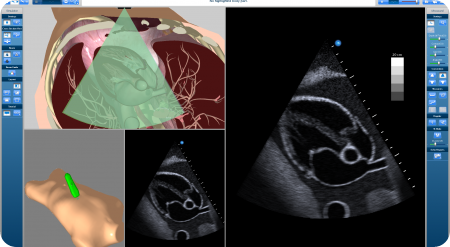

CAE Healthcare’s latest ultrasound simulators, the Vimedix. Courtesy of CAE Healthcare.

The visual technology inspired our virtual reality ultrasound, which is very realistic. Ultrasound is unique in comparison to other imaging methodologies. Unlike CT or MRI scanning where the machine produces the images, ultrasound is completely operator-dependent.

Screenshot of the software actively simulating the real time movement of the trainee. Courtesy of CAE Healthcare.

If you do an echo exam of the heart, you need to be exactly between 2 ribs, avoiding all the shadows and artifacts of the lungs and ribs to capture the right image. Deviate a few degrees or millimeters to the left or right and you miss the image. In our simulator, the manipulation and tracking of the ultrasound probe is extremely accurate. That's key to acquiring the skills that are central to proper ultrasound scanning.